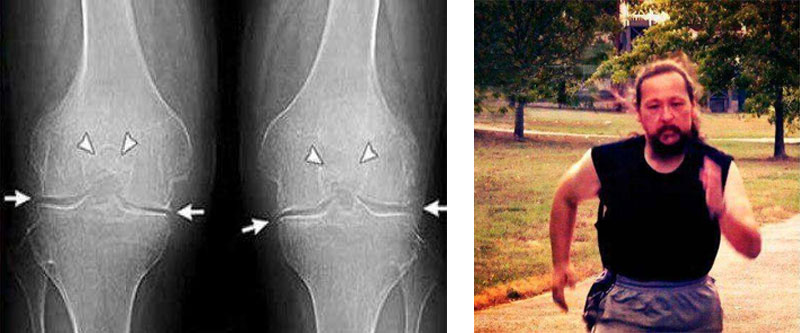

35-η

μέρα:έκανα εξετάσεις και ακτινογραφία του ώμου και του αγκώνα. Δεν υπάρχουν ίχνη αρθρώσεων! Ο

χόνδρος στις αρθρώσεις είναι σαν ενός νεαρού 30 ετών. Ο γιατρός είπε ότι στην προηγούμενη ακτινογραφία

υπήρχε πιθανότατα ένα ελάττωμα, οπότε η διάγνωση της οστεοαρθρίτιδας ήταν εσφαλμένη.